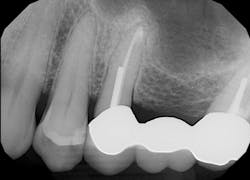

After using a round burnisher and blow test to determine that there was no perforation to the sinus and the membrane was still intact, the laser was used at a spot size of 1.25 mm, on low power mode, and without mist or air to debride the medial superior area of the bony defect. X-rays were taken following immediate placement of bone-graft material to display the site after using Solea to remove bone and granulation tissue (figures 6 and 7). The entire procedure, including the bone graft, took approximately 40 minutes from start to finish.

During post-op visits, final results at the three- and eight-month marks and x-rays taken at eight months revealed optimal outcomes that met the clinical objective (figures 8–10).